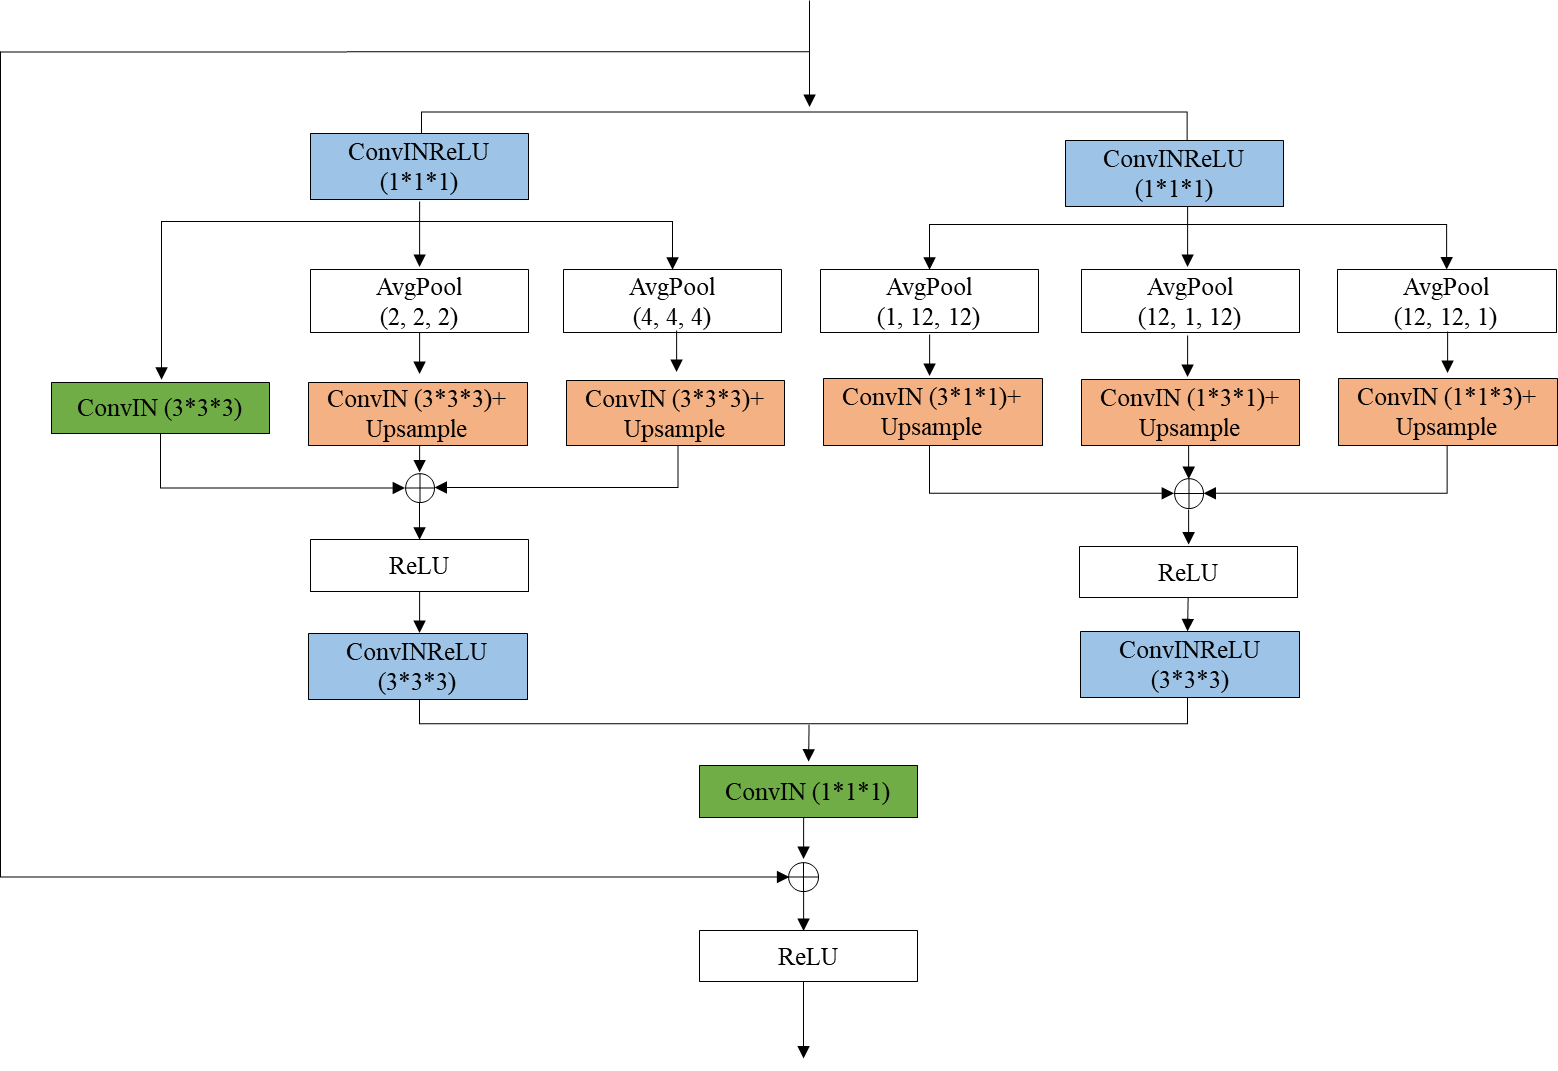

Context block

我们采用基于3D-based mixed pyramid pooling (3D的混合金字塔池化)方法提取背景特征,该方法由标准空间池化和各向异性条带池化两部分组成。标准空间池使用两个平均池,大小分别为2×2×2和4×4×4。anisotropic strip pooling具有三个不同方向的感受域:1×N×N, N×1×N, N×N×1,其中N为上一个编码器模块中feature map的大小。

粗模型初始特征图个数为8,细模型初始特征图个数为16。我们通过添加而不是连接来聚合低级的水平特性,因为前者消耗的GPU内存更少。此外,对于192×192×192输入大小,模型参数的数量是9 MB,失败的数量是333 GB。

- 对比SPP block(https://arxiv.org/abs/1612.01105)、StripPooling block(https://arxiv.org/abs/2003.13328)、AnisotropicAvgPooling block,AnisotropicAvgPooling block具有更优的上下文特征表示能力

- 不同尺度特征的融合方式,本文将upsample+concate+convolution的融合方式,修改为down channel+upsample+add+convolution,后者计算复杂度更低